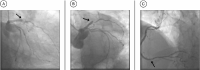

Background Cardiac myxoma is the most common primary cardiac tumor. Although benign, it can cause life-threatening complications due to embolization. Case Presentation We describe an ST-elevation myocardial infarction (STEMI) involving a giant right atrial myxoma and persisting foramen ovale (PFO) in a 64-year-old male patient and report on emergency percutaneous interventional therapy and subsequent cardiac surgery to remove the right atrial myxoma. Conclusion A right atrial myxoma, combined with a PFO, can cause a STEMI. Therefore, every acute coronary syndrome patient should undergo ultrafast exploratory emergency echocardiography to protect the physician from unpleasant surprises.